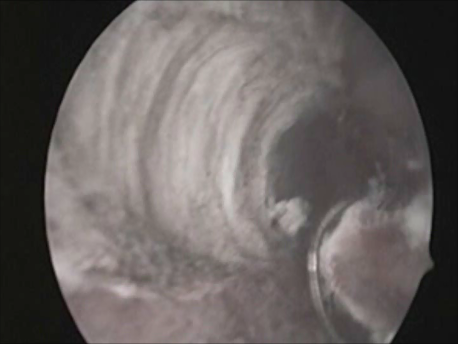

Hysteroscopy means peeping inside the uterine cavity with the help of a fine telescope varying between 2-4mm in diameter. Today a large number of surgeries can be performed via hysteroscopy due to advances in technology and instrumentation. These procedures do not involve any cut on the body and, hence, are virtually painless. The patient can be admitted on the day of the surgery and, if a laparoscopy is not needed, discharged in a few hours.